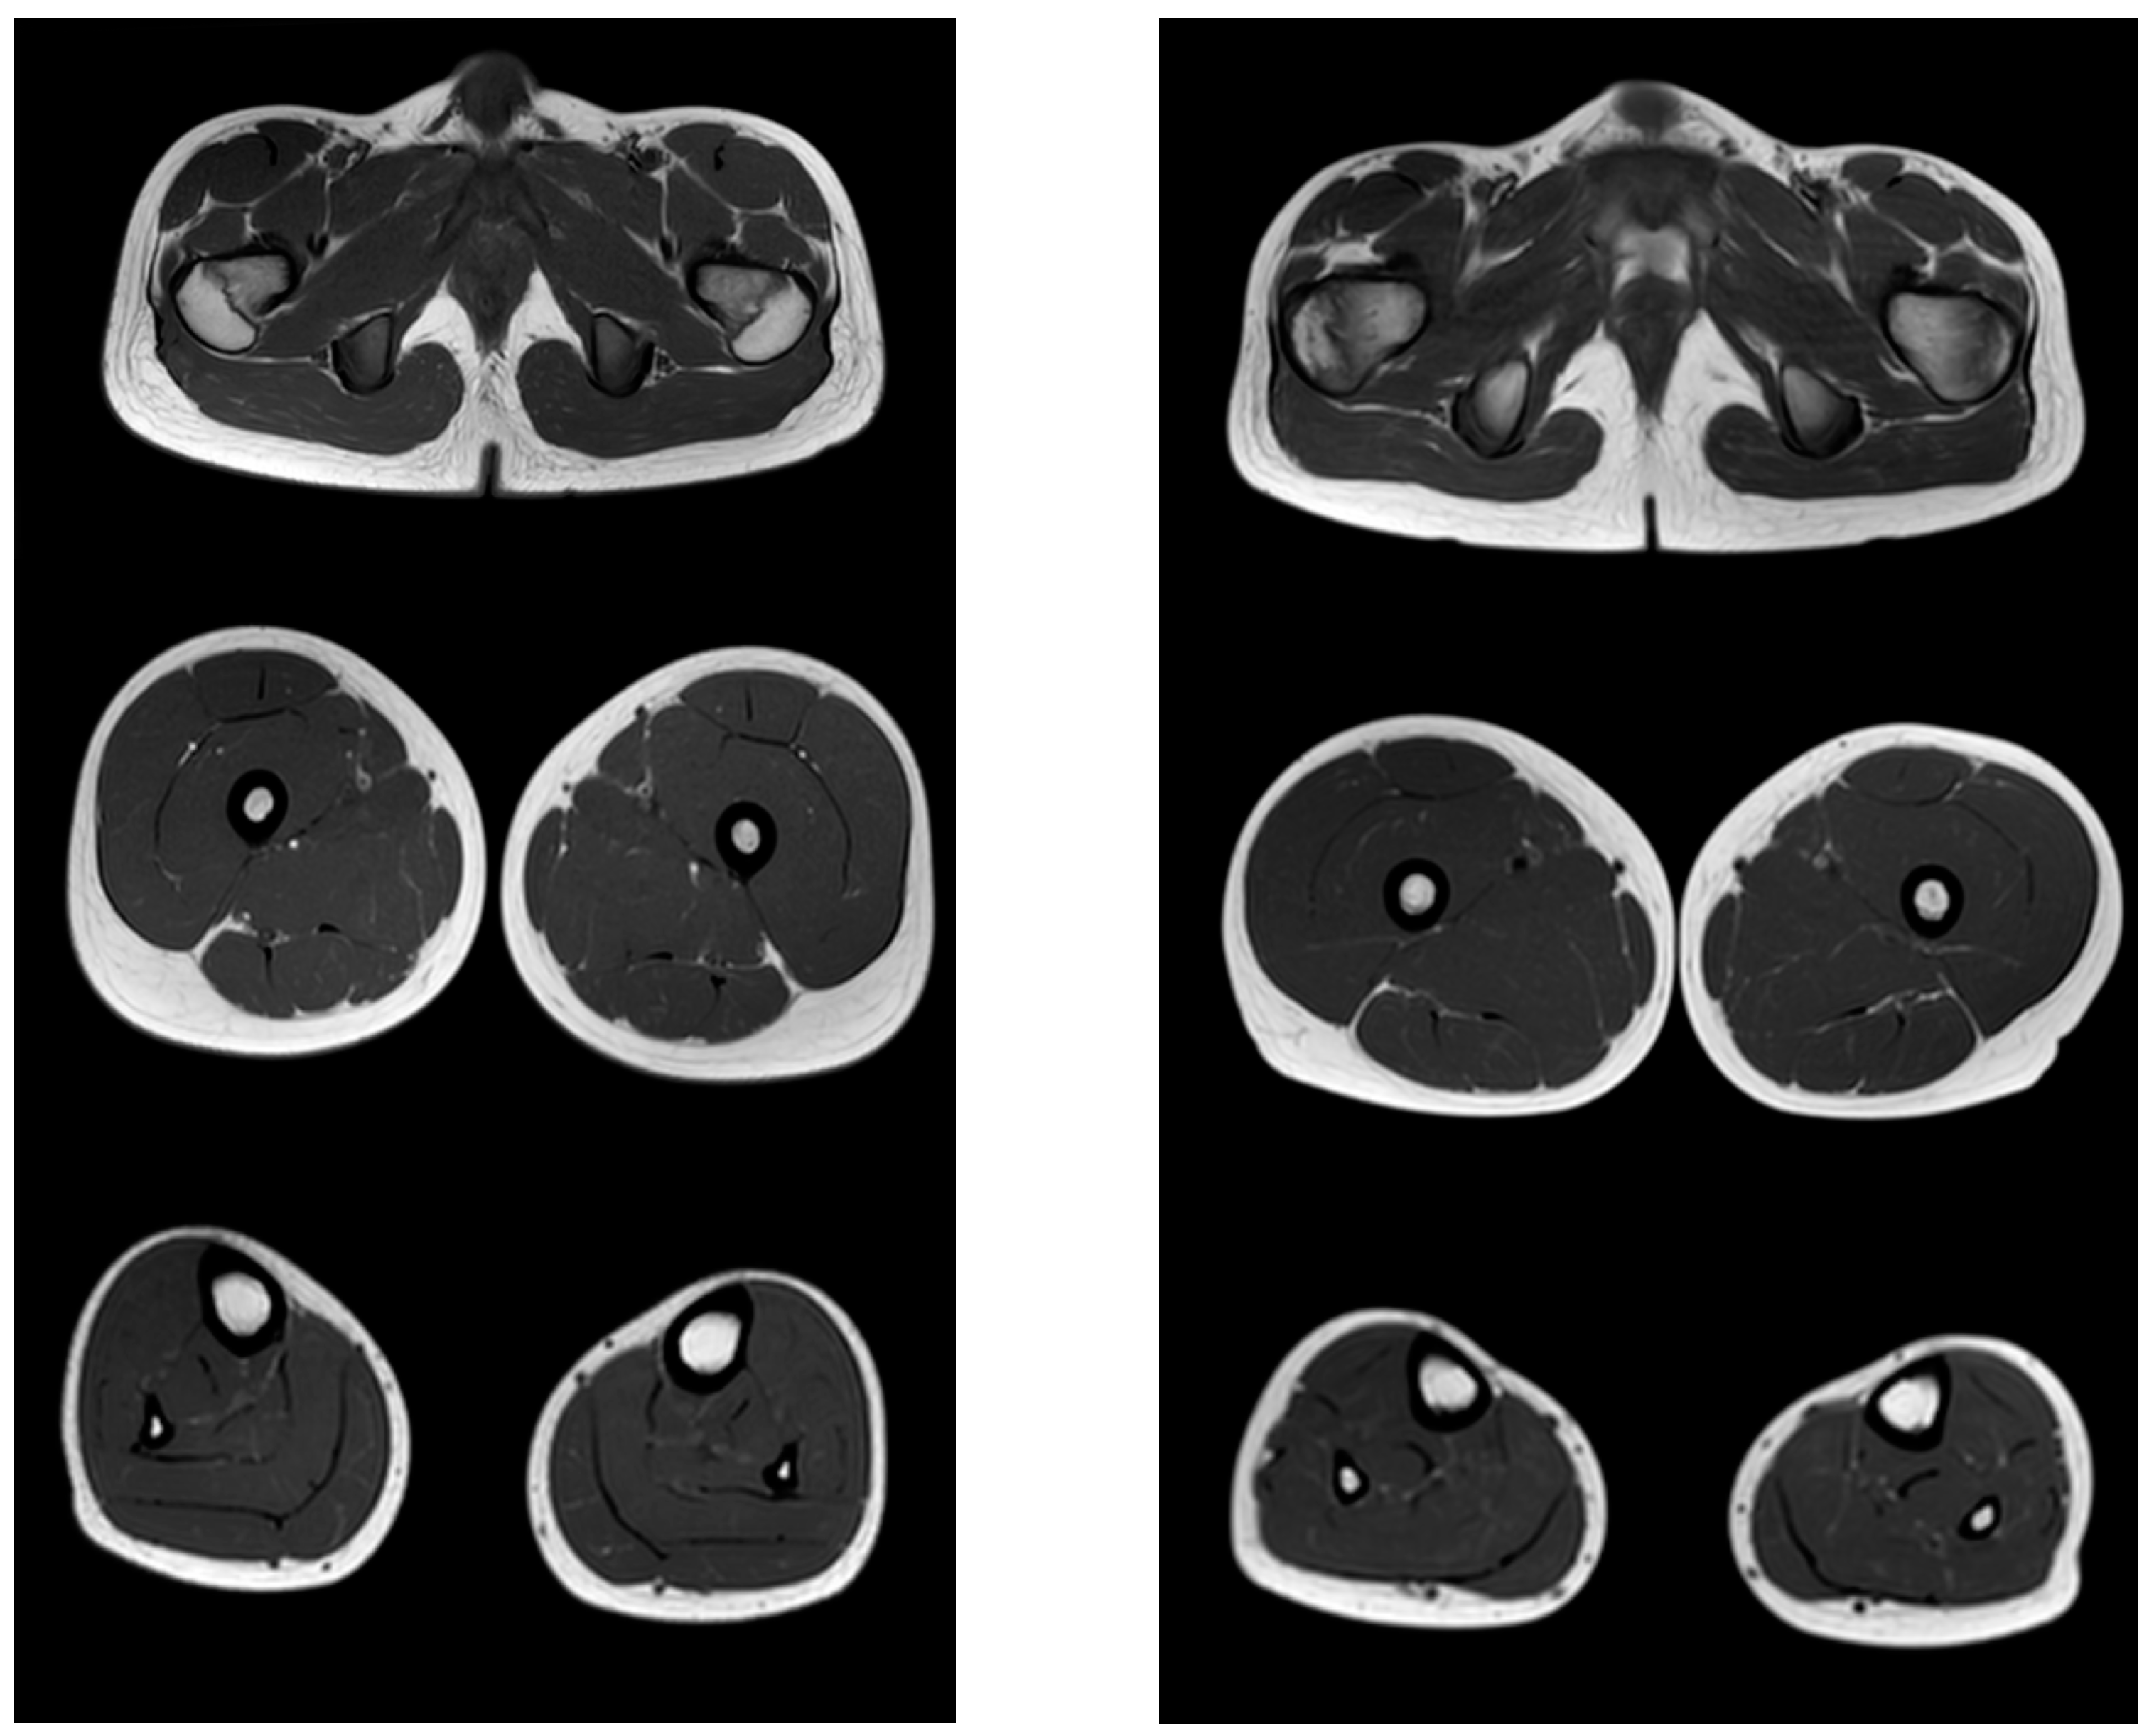

Comparative results of assessing the severity of fibro-fatty degeneration of muscles according to the Mercuri scale (point) of patients in accordance with clinical examples (Figure 3, Figure 4 and Figure 5) are presented in Table 6. For comparison of MR patterns in DMD, Figure 6 shows images of the pelvic level, femoral level, and lower leg level of healthy subjects (volunteers). In contrast to the pathological condition, a clear symmetry, uniformity of the density of muscle tissue, organs of the pelvic level, and the absence of pathological formations draw attention.

Figure 6.

MR images of healthy volunteers 13 years old (left) and 8.3 years old (right). From top to bottom: the pelvic level, the femoral level and the level of the legs.